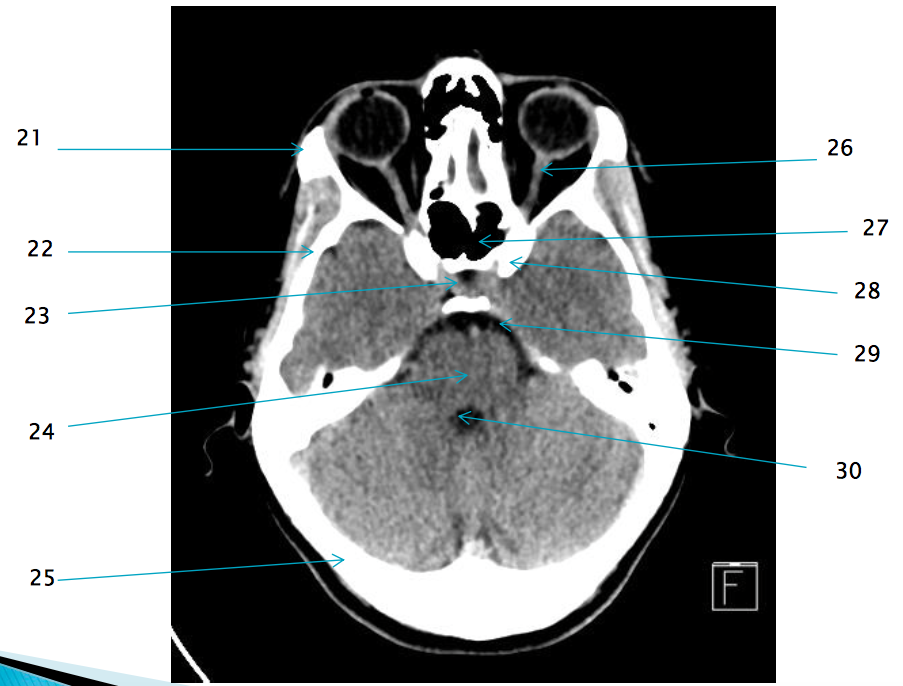

21

22

R temporal bone

28

L anterior clinoid process

29

Pre pontine cistern